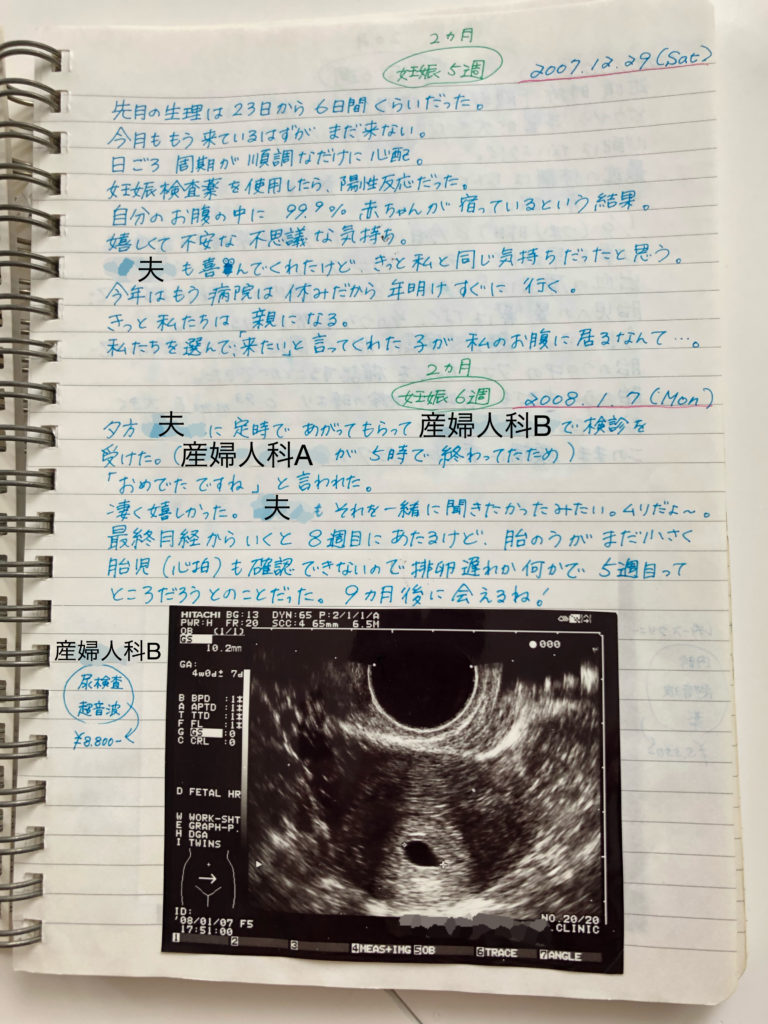

6週2日目の胎嚢にしては小さいとの事で 1月2 4日に少し出血があった 妊活 教えて Goo

2度の流産と妊活記録vol 2 妊娠6週やっと胎嚢見えたが8週で1度目の流産へ やっぱり家が好き

6週目 胎嚢確認 ルルのお部屋 楽天ブログ